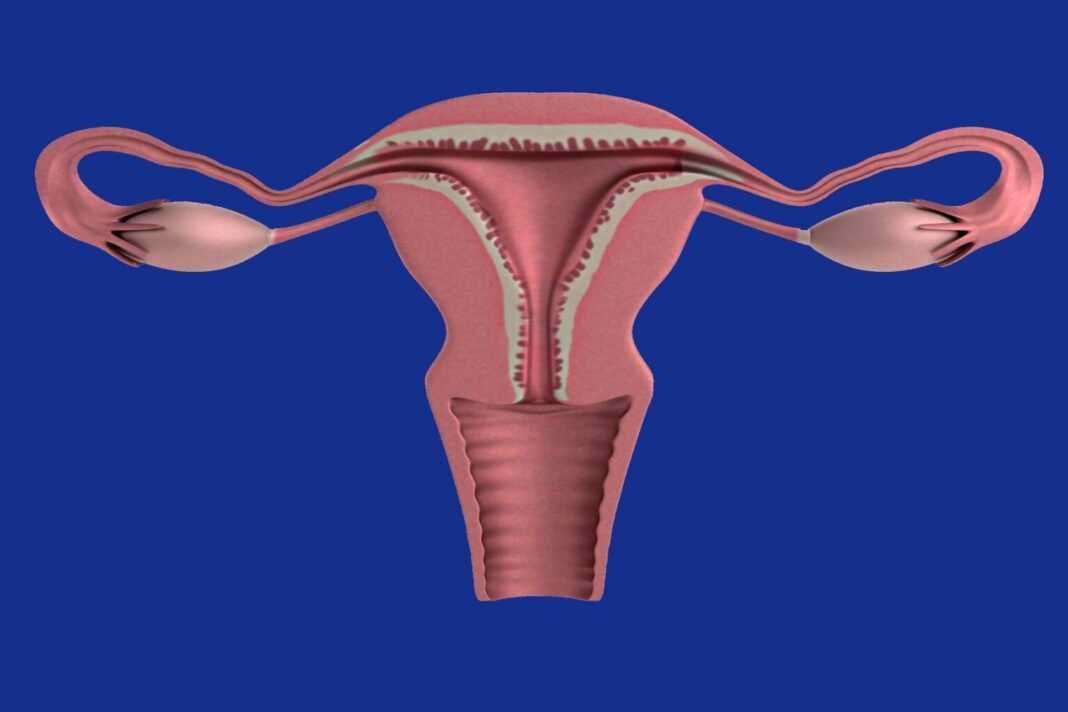

- Πολυκυστικές ωοθήκες. Οι ωοθήκες σας μπορεί να είναι μεγαλύτερες. Πολλά ωοθυλάκια που περιέχουν ανώριμα ωάρια μπορεί να αναπτυχθούν γύρω από την άκρη της ωοθήκης. Οι ωοθήκες μπορεί να μην λειτουργούν όπως θα έπρεπε.